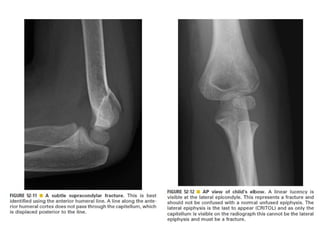

Skeletal trauma was presented by Dr Laith Fadhel with reference to Grainger's Diagnostic Radiology textbook. The presentation covered skeletal trauma as assessed through diagnostic radiology techniques. Key findings and treatments for skeletal injuries were likely discussed.